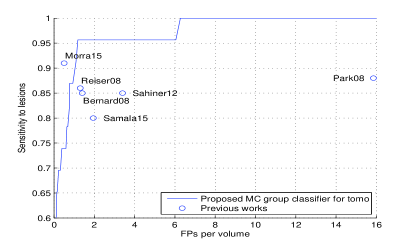

4.2 Performance on DBT Volume Image

The proposed system was tested on an independent GE SenoClaire DBT volume set with 23 labeled malignant MC groups and 42 normal cases, no individual MC labeled and no other abnormalities visible. Figure 4(a) shows the MC group detection FROC and the comparison with other previously published MC group detection performances on DBT [1, 2, 3, 4, 5, 10]. Figure 4(b) shows two successful detections. The proposed system shows state-of-the-art performance compared with these published works, although all these works including ours were tested on different and relatively small datasets ( cancerous lesions). We need to emphasize that there was absolutely no training or fine-tuning on the DBT data for our system, while other works were not restricted to develop on small numbers of DBTs that could cause overfitting. The study from Morra et al. [10] reported better performance, but the authors used Hologic cases with two-view DBT volumes per breast, which may double the chance to find MC groups, while the GE set we were using had only one DBT view available. Furthermore, there is no method details disclosed in [10].